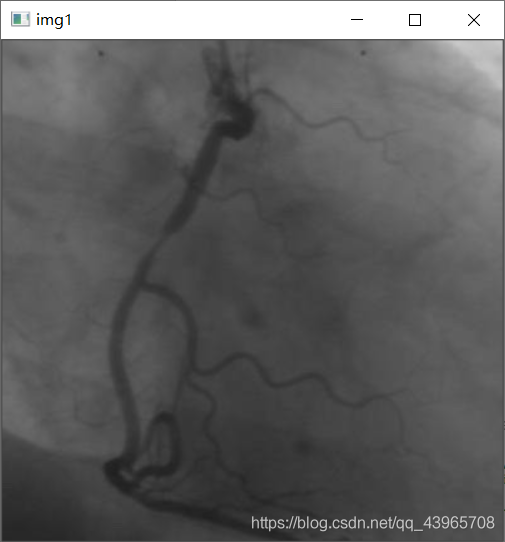

# 显示灰度图

img = cv2.imread(r"C:\Users\pc\Desktop\vas0.png",0)

cv2.imshow("img1",img)

运行结果